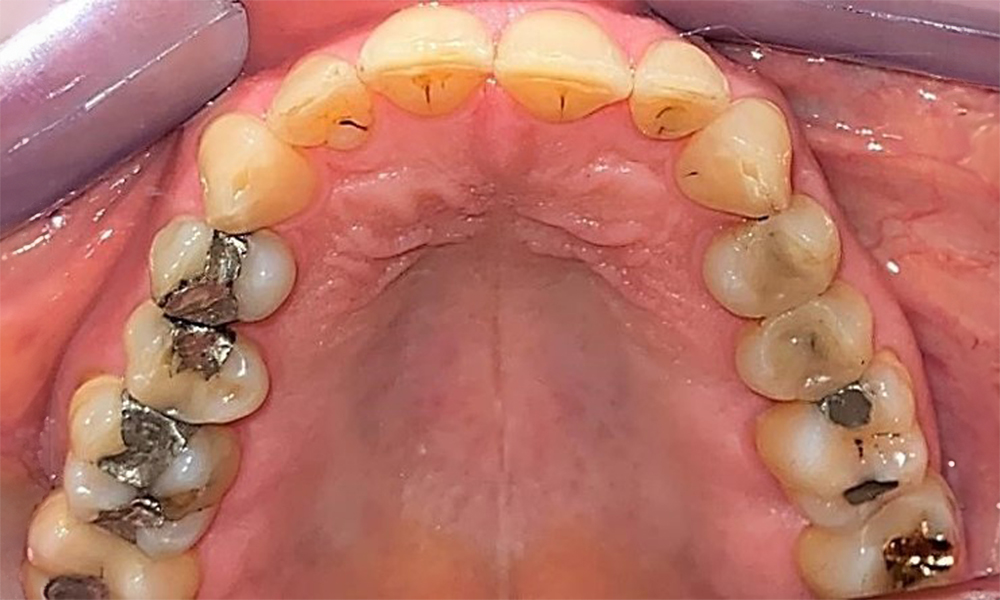

Occlusal view of the maxilla. Insufficient amalgam filling of 14 with a marginal gap.

Fig. 5 Occlusal view of the maxilla. Insufficient amalgam filling of 14 with a marginal gap. © Dr R. Krapf

The patient has a full dentition with 28 teeth, which includes amalgam and composite fillings in the molar and premolar regions. There is a visible clinical marginal gap present on tooth 14. Tooth 27 has an adequate gold inlay. There are also generalized attritions and abrasions. (Fig. 2, Fig. 3, Fig. 4, Fig. 5, Fig. 6)

The patient has stage II, grade B periodontitis (5). At 1 to 3 mm, the clinical probing depths were within the physiological range. Localized probing depths of 5 mm were observed on the mesiopalatal aspects on both 17 and 27. There are generalized recessions of 1–3 mm with partial loss of the interdental papillae (Fig. 2, Fig. 3, Fig. 4)